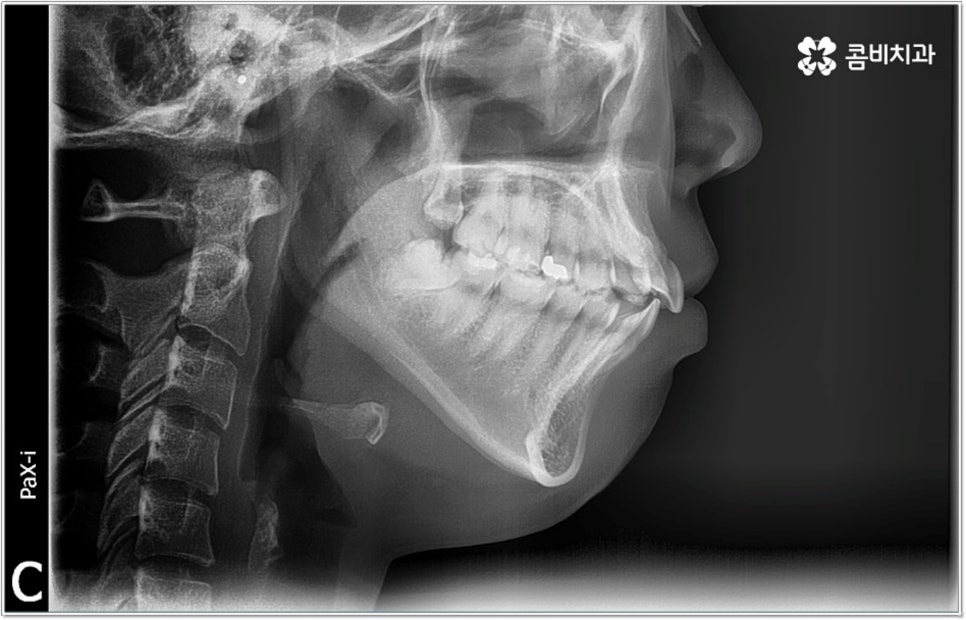

잘 아시다시피 교정이란 치아에 교정 장치 (브라켓) 를 부착하고 와이어에 교정력을 걸어 필요한 방향으로 치아를 이동시킴으로써 고른 치열과 올바른 교합을 가진 정상적인 구강 구조를 회복하는 치과 진료를 의미하는데요, 말씀드린 것처럼 부정교합에는 다양한 형태가 있고 또한 환자분들마다 심각한 정도가 모두 다르기 때문에 현 상태를 면밀하게 체크하고 맞춤 교정 치료 계획을 세우는 것이 무엇보다 중요하다고 할 수 있습니다. 즉 3D CT 와 같은 정밀 진단 장비를 갖추고 있는 치과에서 교정 관련 임상 경험이 풍부한 숙련된 의료진과 함께 치료를 진행하는 것이 필수적이라고 할 수 있어요. 전체 방향 및 세부 플랜을 세울 때 각 환자에 맞게 치아의 이동 속도에 무리가 가지 않도록 하기 위해서 연령이나 발달 상황, 진행 상황을 면밀하게 살펴보는 것이 필요하며 또한 구강 내 공간 유무 및 부정교합 정도에 따라 발치 또는 비발치치아교정 여부를 결정하게 될 거예요.

만약 치아가 이동할 범위를 계산해 봤을 때 공간이 충분하다면 굳이 치아를 뽑지 않고 비발치치아교정 과정으로 치료할 수 있어요. 제일 뒤에 있는 어금니를 더 후방으로 이동시키거나 치간 삭제, 악궁확장장치 등으로 치아 사이를 벌려서 이동 공간을 확보할 수 있으면 비발치치아교정 이 가능한 거예요. 이 때 부정교합이 심각하거나 악골이 치아에 비해 많이 작은 경우, 구조적인 원인을 개선할 필요성이 있는 경우 등 발치 교정을 하는 것이 꼭 필요한 케이스라면 치아를 뽑아주어야 하며, 환자분들의 상황에 따라 다르지만 보통은 소구치를 발치하는 경우가 많이 있습니다.